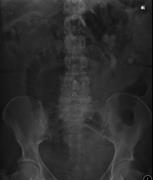

An atypical case of large bowel obstruction

Kaylie E. Hughes and James Arthur